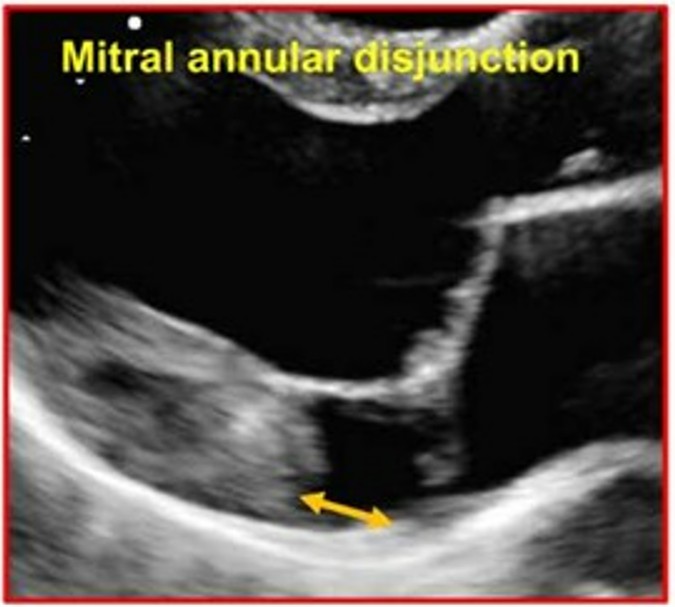

A disjunção do anel valvar (MAD) foi considerada como presente quando houve separação entre a borda posterior do miocárdio e a junção do folheto posterior com o átrio esquerdo (AE).